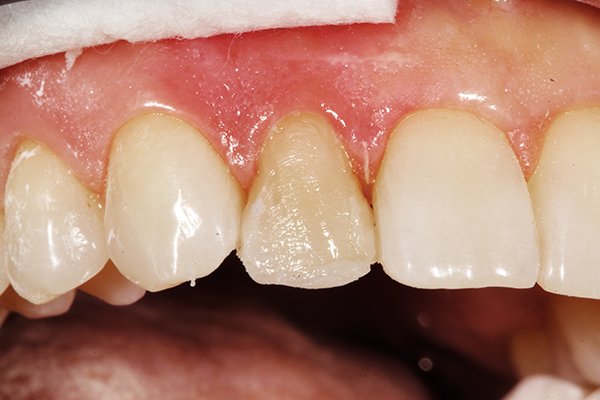

ONE COAT 7 UNIVERSAL (COLTENE) bonding agent was applied/dried for 25 seconds and cured for 10 seconds (Fig. 7). Using a putty matrix, a thin layer of translucent shade was adapted and sculpted to create a lingual incisal “scaffold” to frame the primary anatomy of the tooth as well as the lingual occlusal anatomy (Fig. 8).

Fig. 8 Fig. 9

The A1/B1 Duo Shade was applied and layered using a compule of material on the facial surface following the two planed anatomy of the tooth as well as the mesiodistal line angles of the contralateral tooth and buccal contours of the adjacent teeth (Fig. 9).